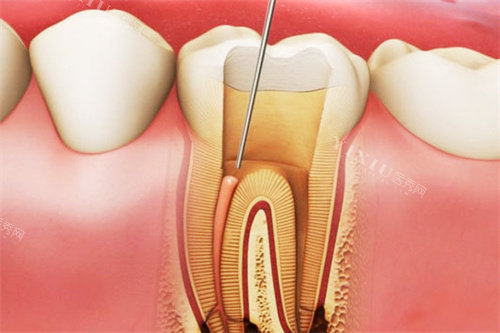

确定方案后,护士小姐姐先带我拍了牙齿的 CT 和照片,然后开始取牙齿模型。取模的过程比我想象中轻松,就是往嘴里放了软软的材料,咬几分钟就好了。接着就是磨牙环节,这是我非常紧张的一步。医生一边操作一边安慰我:“别担心,只会磨掉薄薄一层,就像给牙齿修个小边,不会有明显痛感。” 果然,打了麻药后,几乎没什么感觉,全程能感受到医生手法特别轻柔、细致。

磨完牙后,医生给我戴上了临时牙贴面,虽然样子有点奇怪,但至少不影响正常生活。大概过了一周,定制的全瓷贴面就做好了。复诊那天,医生小心翼翼地把临时贴面取下,再将新贴面一点点粘贴、调整。神奇的是,当镜子里出现一口洁白整齐的牙齿时,我差点尖叫出来!新牙齿不仅颜色自然,和真牙几乎没差别,而且咬合也完全没问题,完全不会有异物感。